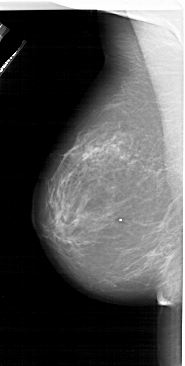

A_1620_1.LEFT_MLO

LESION_TYPE MASS SHAPE IRREGULAR MARGINS SPICULATED

ASSESSMENT 5

SUBTLETY 3

PATHOLOGY MALIGNANT